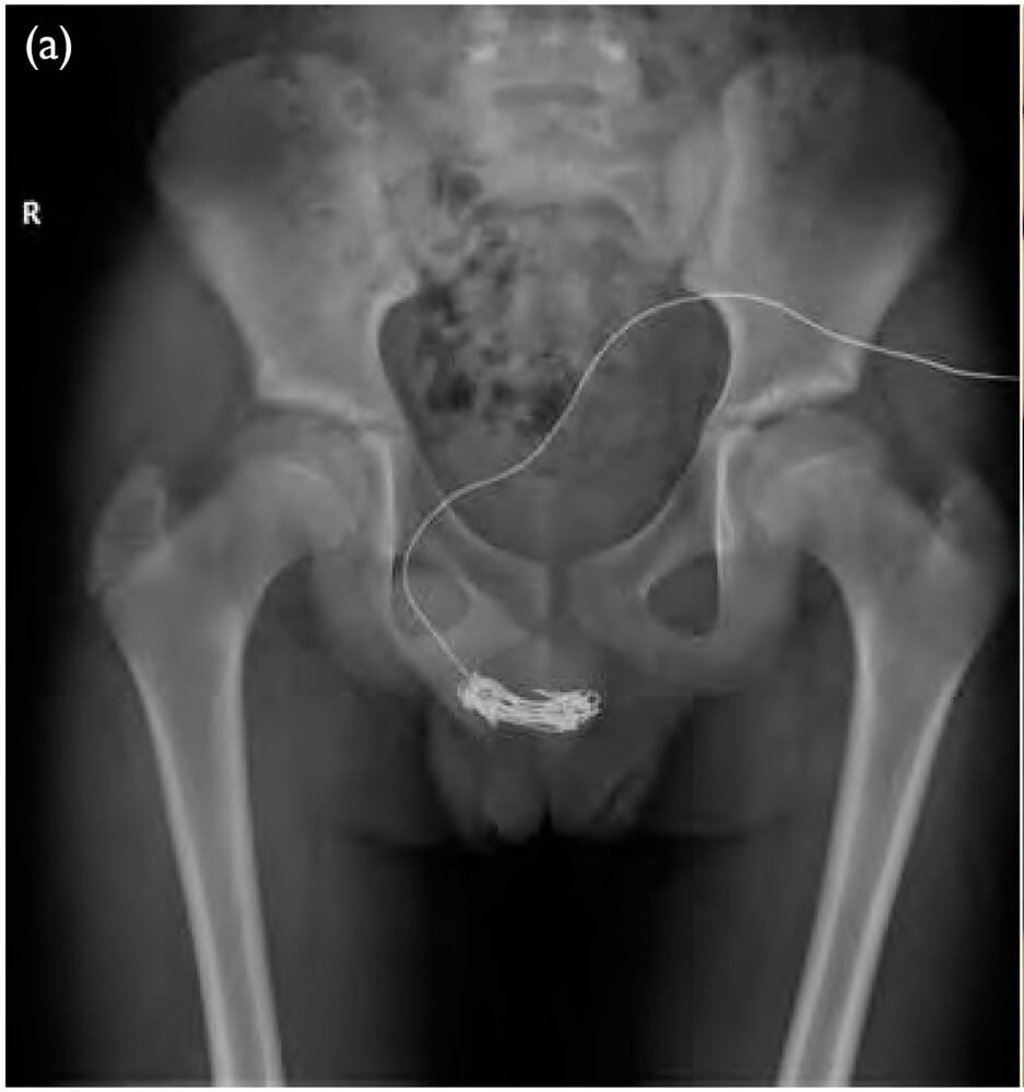

Medical examination showed a tangle of electrical wire inside the urethra with 20cm (7.9 inches) protruding via the opening. Surgeons removed the object and reconstructed the damaged area.